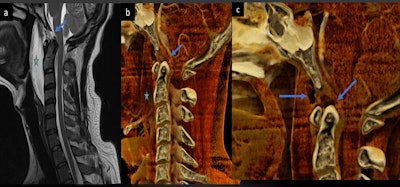

- 24-year-old passenger in a motor vehicle accident. The patient presented with atlanto-occipital dissociation, initially measured as 12 mm on plain radiographs but later found to be 9.6 mm on cinematically rendered CT scans. Magnified views of the cinematically rendered images revealed the severity of a tear in the tectorial membrane and a disruption of the apical ligament, both of which were very difficult to appreciate on routine CT scans. The soft-tissue injuries were subsequently confirmed on MRI scans.